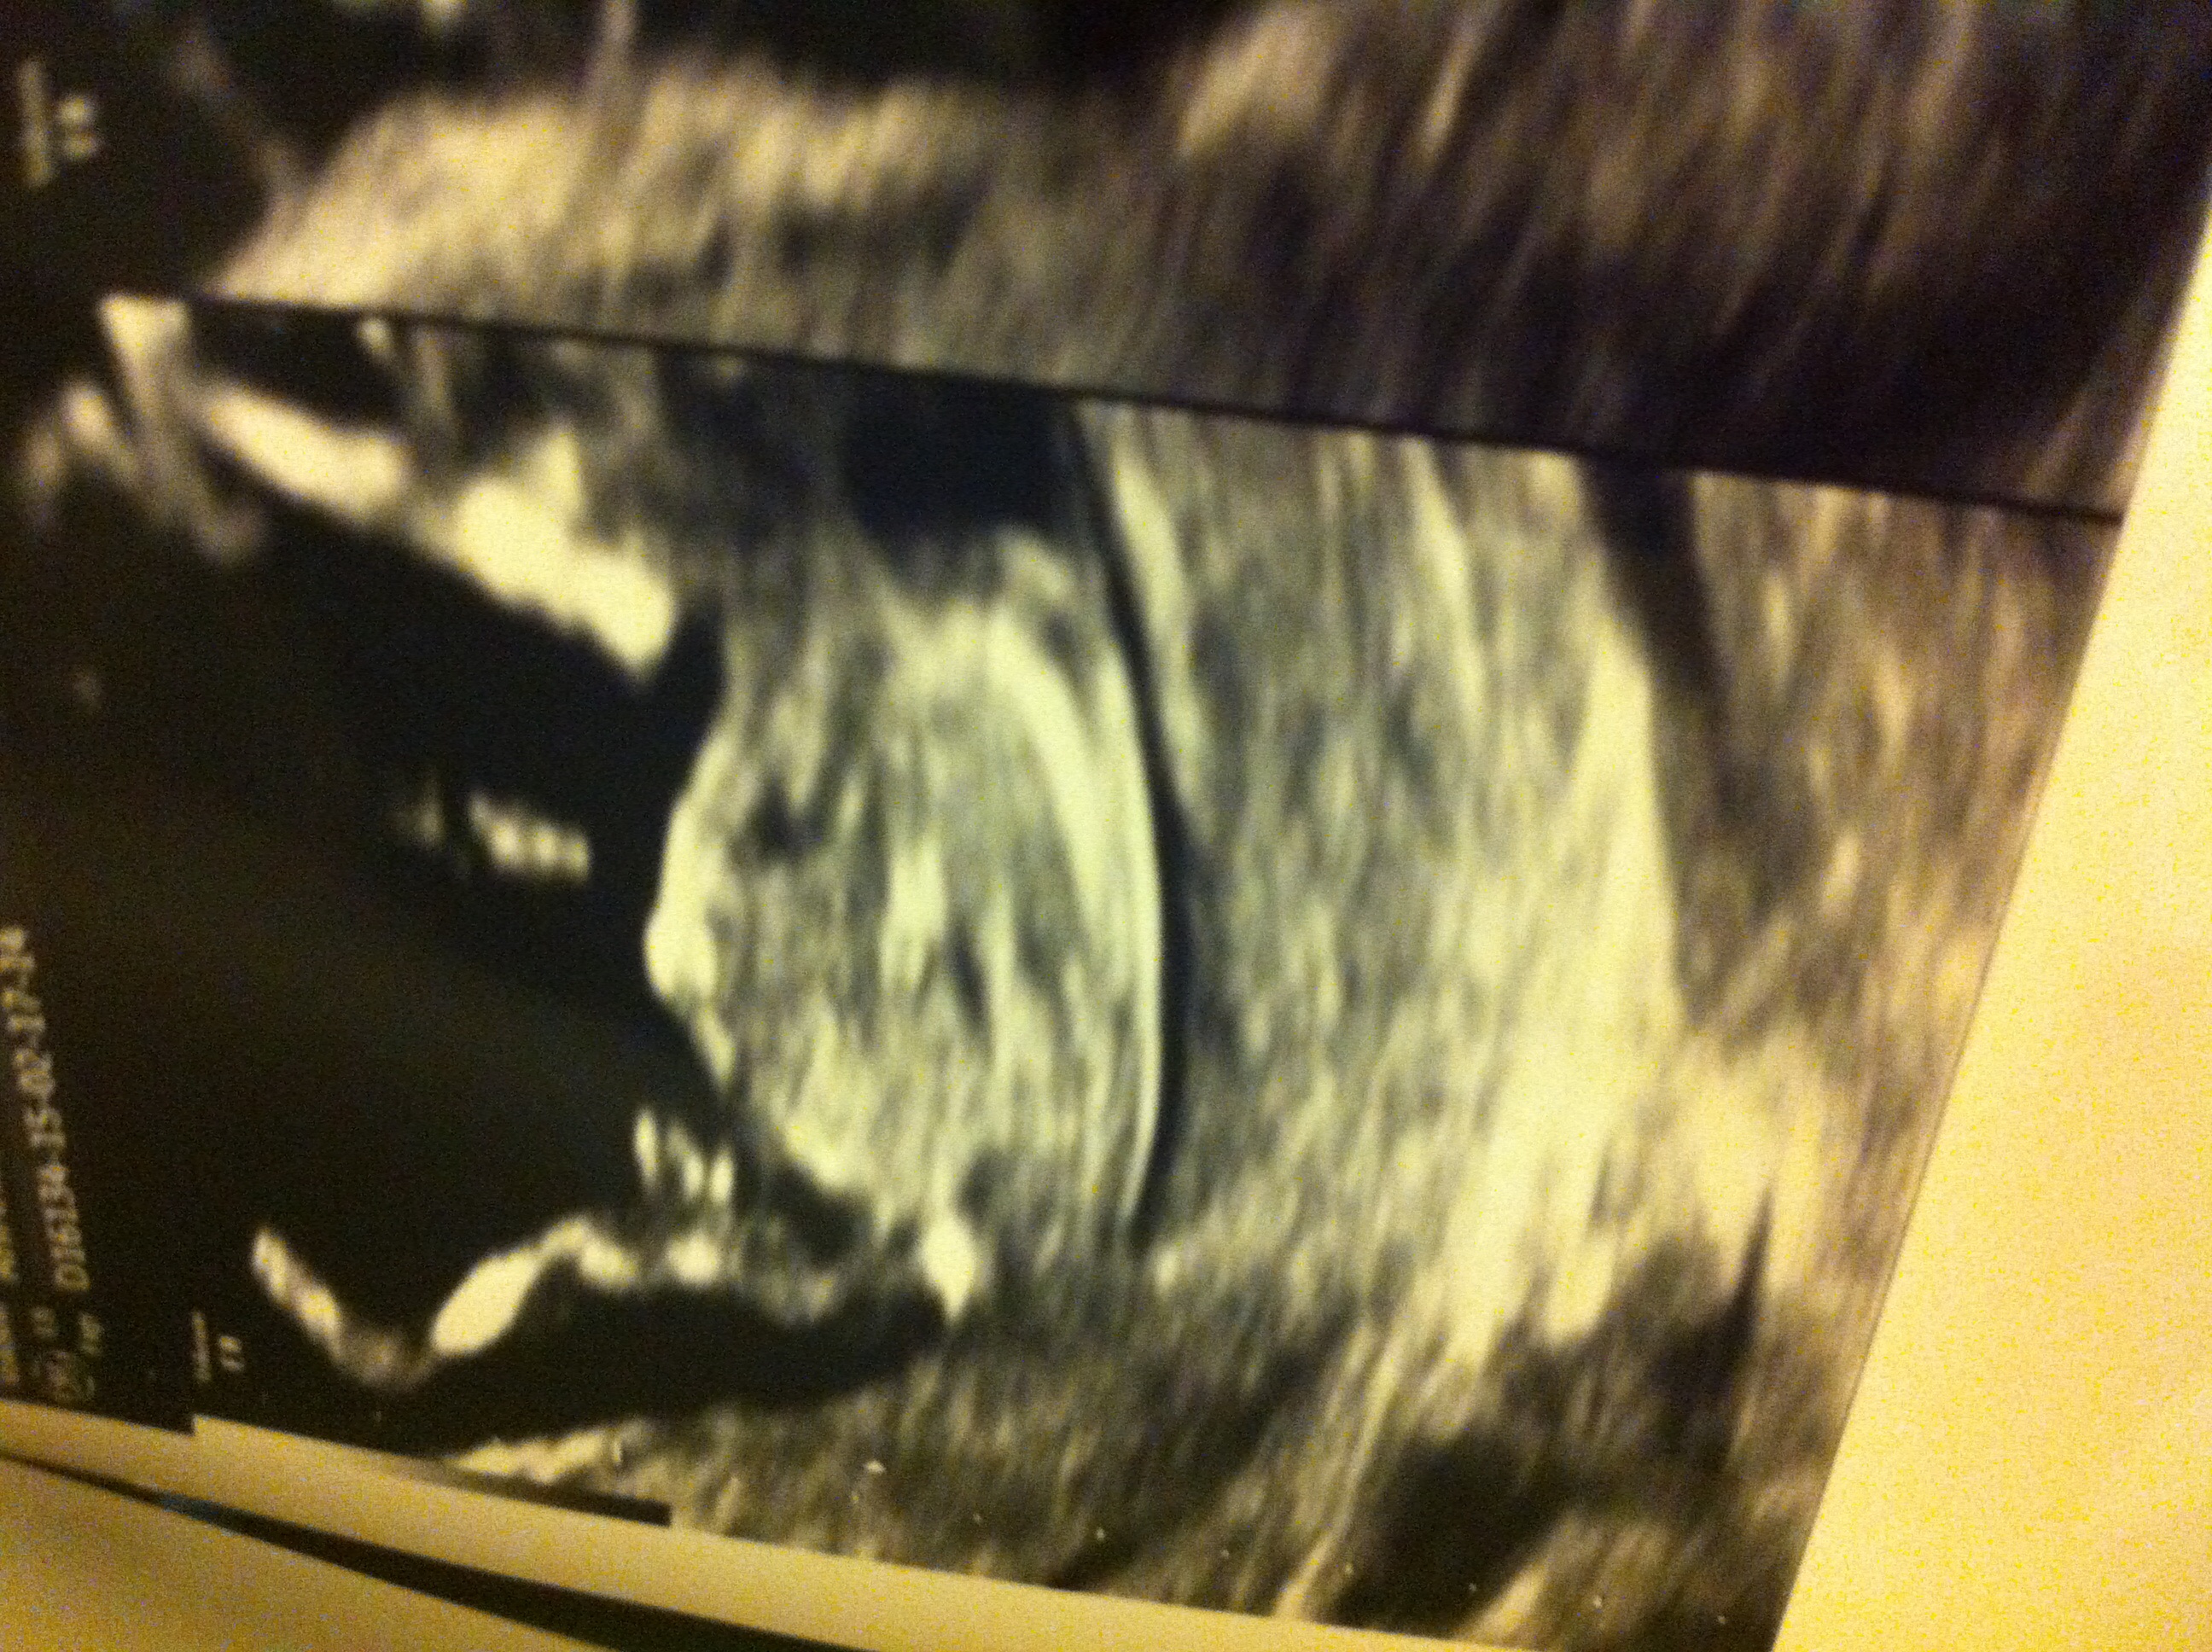

Attachment 23820This is my 12 weeks 2 days scan. Any guesses?2nd image is a shot of legs. Many thanks. Attachment 23819